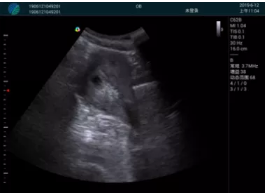

病例一:

清晰顯示孕囊,通過軟件包計(jì)算孕齡7w+6d

M20實(shí)時引導(dǎo),術(shù)中清晰顯示孕囊被破壞和抽吸針的過程,清晰顯示吸引針

抽吸結(jié)束后縱切子宮,孕囊已被完全抽吸,未見明顯殘留

橫切子宮,發(fā)現(xiàn)右側(cè)宮腔靠近宮角處有少許脫模樣殘留

M20引導(dǎo)下,抽吸針找到右側(cè)宮角處再次清掃

二次抽吸后再次進(jìn)行超聲檢查,宮腔未見殘留,宮腔線清晰顯示

超聲引導(dǎo)下可視化人流是技術(shù)安全性的保障,一般對人流術(shù)設(shè)備預(yù)算不高,M20具備婦產(chǎn)科軟件包,且穿透力圖像質(zhì)量好,既滿足人流引導(dǎo)需要,也可用于床旁超聲的需求。